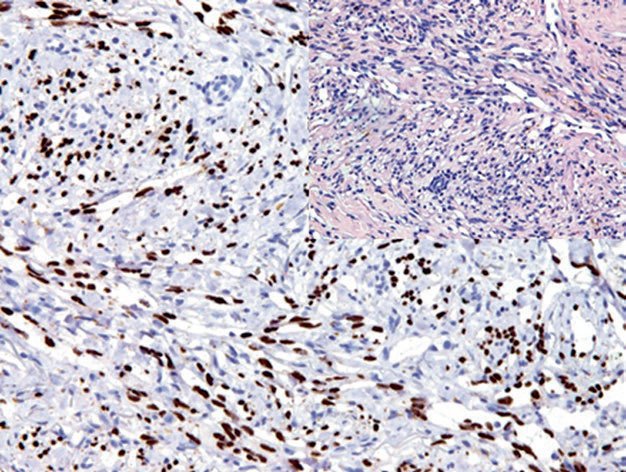

图3. 血管肉瘤,肿瘤细胞的细胞核强阳性表达ERG。

除内皮细胞肿瘤外,ERG还表达于部分不成熟的造血细胞。具有TMPRSS2-ERG易位的前列腺癌中,ERG也是阳性的。对于间叶性肿瘤来说,某些形态学类似血管性肿瘤的其他间叶性肿瘤有该指标的表达,具体如孤立性纤维性肿瘤、纤维性脑膜瘤、上皮样肉瘤。某些类型的淋巴瘤中,也有少量病例具有ERG的表达。